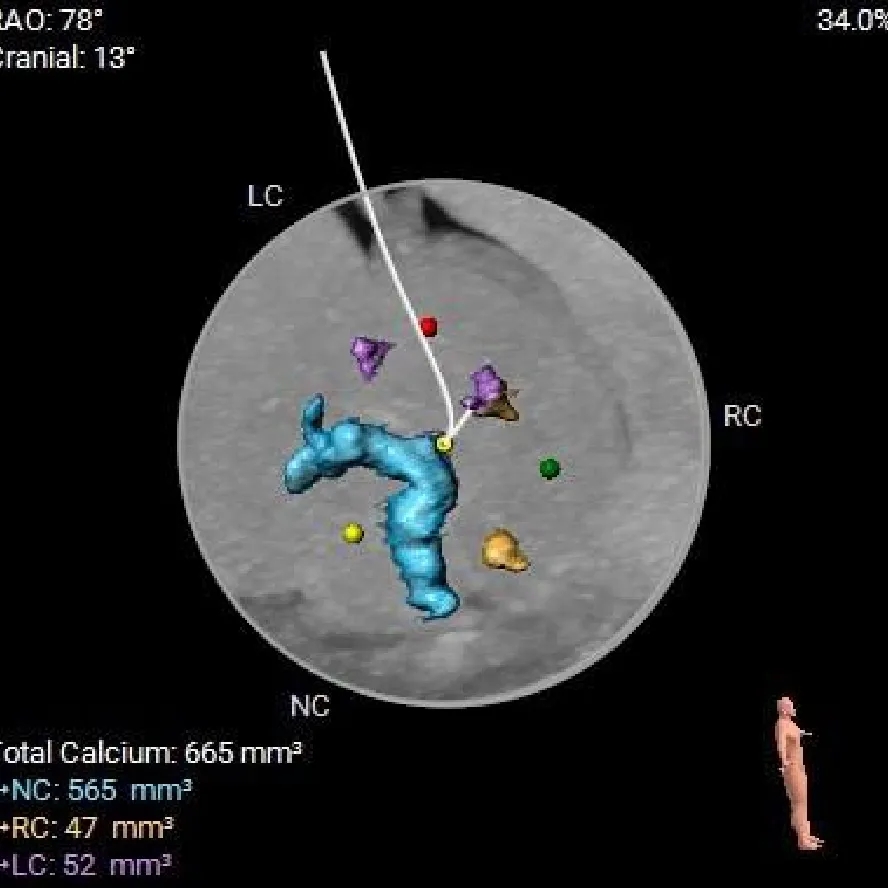

术前CT分析

TYPE-1L-R融合二叶瓣,中-重度钙化,流出道收口型,升主动脉未见扩张;

双侧冠脉高度可,冠脉阻挡风险不高;

瓣环水平夹角75°,横位心;

外周血管内径充足,双侧髂动脉及腹主动脉可见明显钙化,无明显迂曲;

根据瓣环及瓣上结构选择 ScienCrown TF25mm瓣膜。

主动脉根部测量

Annulus

22.8mm

LVOT

20.4mm

钙化积分:

665mm3

SOV:

33.1*35*34.3mm

STJ:

34.5mm

AAO:

41.2mm